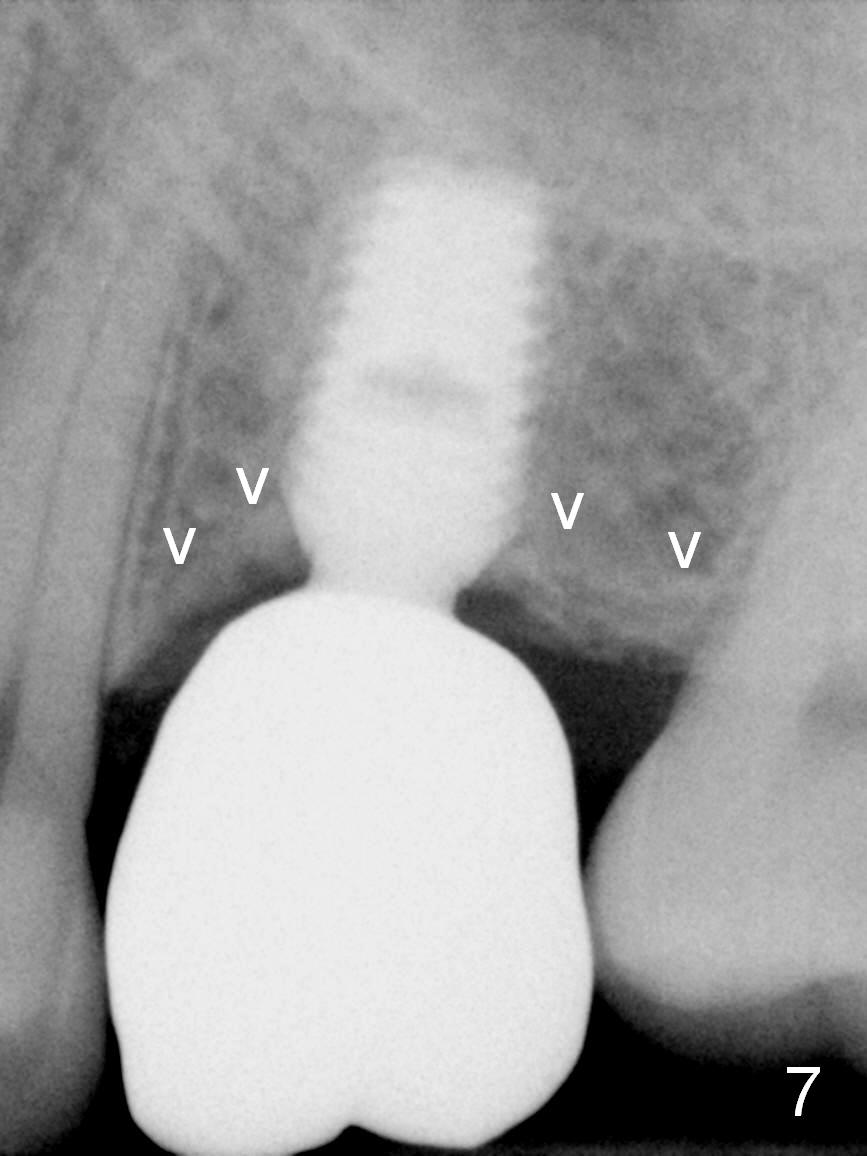

A 49-year-old man is an engineer. The tooth #14 is missing (Fig.1,2). He wonders how a one-rooted implant can replace a three-rooted tooth. Anyway, osteotomy is initiated at the site with 2.5 mm reamer in place (Fig.3). A 5x8 mm Bicon implant is placed (Fig.4). Seven and a half months later, the bone density next to the implant plateau appears to increase (Fig.5 arrowheads, as compared to Fig.4). The beauty of Bicon implant is that the crown (Fig.6 C) can be extraorally cemented to the abutment (A) prior to re-seating. Two years and 3 months post cementation, while no residual cement is visible, the bone density at the crest has increased (Fig.7 arrowheads). The crown is de-cemented 4 years 4 months post cementation; it appears that the abutment is small and short (5x2 mm 10 degree stealth). The bone density of the cortex around the implant (Fig.9 ^) is higher than that at #15 and #3.